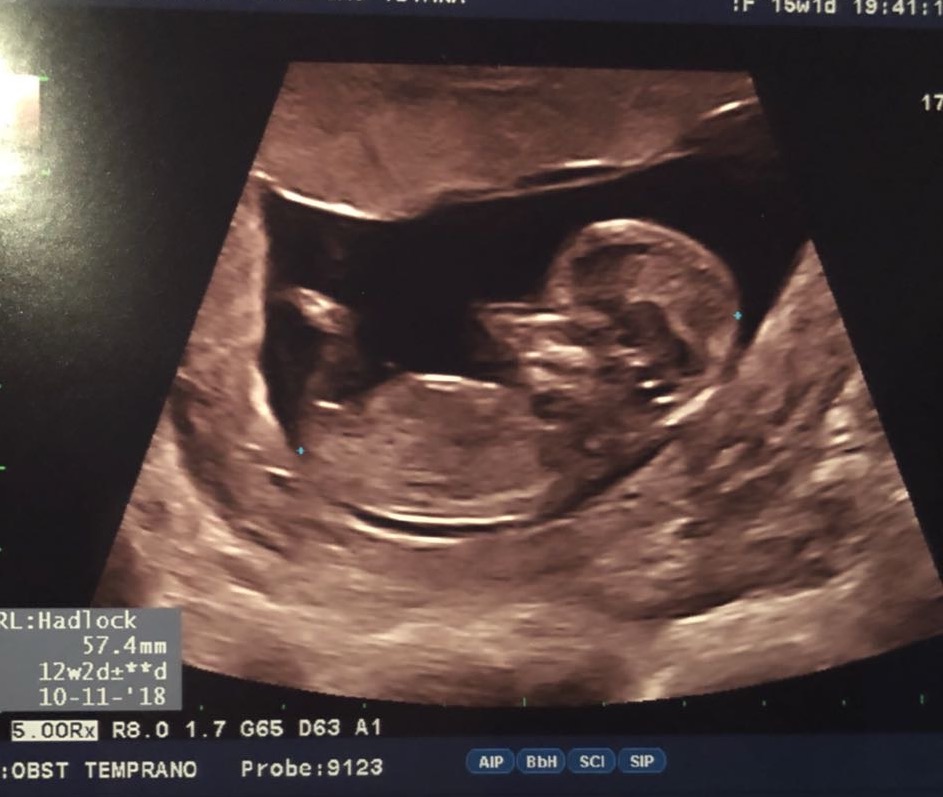

Ellos se prepararon muy bien ya que leían, asistían a cursos y talleres, que les daban las herramientas y conocimientos para la responsabilidad de ser padres. Su madre no era muy comunicativa que digamos, mas nosotros no dejábamos de preguntarle que les decía el ginecólogo o alguna noticia en especial cuando sabíamos que tenia cita, y siempre la respuesta era: que todo OK. Por preguntones logramos que nos mandara algún eco como el de la imagen mas abajo. Wow, la primera foto de la criatura! Eso fue maravilloso y mas cuando los comparamos con los ecos de nuestros tiempos. Aunque todo fuera “OK” no dejábamos de orar para que todo siguiera OK y que este bebe naciera sano.